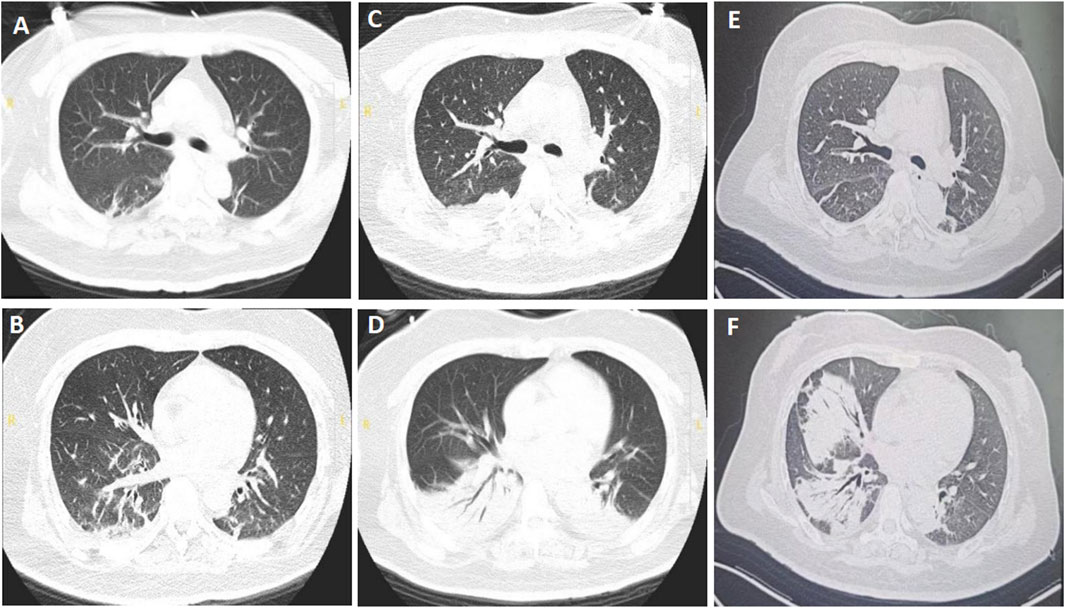

Upon admission, the patient had a fever of 38.4 °C and tachycardia (148 beats/min), with a normal blood pressure (106/64 mmHg). The physical examination showed moist crackles in both lungs, decreased bowel sounds, decreased muscle strength of both upper and lower limbs (grade 3/5), and reduced tendon reflexes of the extremities. Blood cytometry revealed leukocytosis (17.15 × 109/L) with normal erythrocytes and platelets. Other parameters such as liver and kidney functions were normal. The chest CT taken on July 19th showed multiple ill-defined linear and patchy opacities in both lower lobes (Figures 2A,B). BoNT-A antitoxin was administered at a dose of 10,000 IU once daily. Klebsiella pneumoniae was cultured from sputum when the patient was hospitalized in the county hospital, so ertapenem at a dose of 1 g once daily was used to treat the pneumonia when she presented to our hospital.

Figure 2. Chest computed tomography of patient B. (A,B) Multiple ill-defined linear and patchy opacities in both lower lobes, taken on 19 July 2024. (C,D) Enlarged consolidation areas of both lower lungs, taken on 29 July 2024. (E,F) Infiltrating fields in the left lung were partially absorbed, while those in the right lung enlarged, taken on 15 August 2024.

The patient was successfully weaned from the ventilator at 10:20 a.m. on July 21st, and the physical examination showed that the muscle strengths of limbs were grade 4/5. Piperacillin tazobactam at a dose of 4.5 g every 8 h was used to replace ertapenem based on the normal temperature and improved leukocytosis (12.14 × 109/L). However, she experienced dyspnea and difficult expectoration on the second day, with a worsened arterial gas analysis results with a pH of 7.08 and PaCO2 of 150 mmHg, so she was reintubated to improve the retention of CO2 at 22:56 on July 22nd. Due to the emergent hypercapnic respiratory failure, reintubation rather than tracheostomy was performed based on the recommendations (Nelson et al., 2010; Lee et al., 2024). On July 29th, extended-spectrum beta-lactamases (ESBLs)-producing Klebsiella pneumoniae was cultured from sputum, and chest CT showed that the consolidation areas of both lower lungs were significantly enlarged (Figures 2C,D), then imipenem cilastatin at a dose of 0.5 g every 6 h was used to replace piperacillin tazobactam. The patient’s condition improved thereafter and was weaned from the ventilator on July 31st. High-flow nasal cannula oxygen therapy (HFNC) was performed at a flow rate of 35 L/min and a concentration of 40%. BoNT-A antitoxin was stopped on August 1st. Aspergillus niger was detected from bronchoalveolar lavage fluid with a glactomannan test result of 1.47, so voriconazole at a dose of 200 mg every 12 h (the first two doses were 400 mg) was initiated on August 2nd. The patient was discharged and transferred to a respiratory specialist hospital for continued therapy based on her improved condition on August 7th.

The patient received treatment of cefoperazone sulbactam and voriconazole for 2 weeks in the respiratory specialist hospital, and the chest CT taken on August 15th showed that the infiltrative fields in the left lung were partially absorbed, while those in the right lung enlarged (Figures 2E,F). She discharged from that hospital with slight productive cough and normal muscle strength of limbs. Oral voriconazole at a dose of 200 mg every 12 h was prescribed based on her improved symptoms and normal leukocyte count (4.21 × 109/L). Ptosis was still present when she visited the outpatient department for review on 12 September 2024. And the electromyography showed fibrillation and positive sharp waves of the left orbicularis oculi muscle and right first interossei indicating myogenic lesions, without increment on high-frequency RNS or decrement on low-frequency RNS (Figures 3A–D). The patient finished a 3-months course of anti-fungal treatment with voriconazole without taking another chest CT. Ptosis disappeared 3 months after her discharge, and no symptoms or signs were reported when the last followup was taken on 18 March 2025.